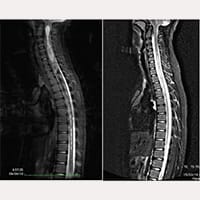

Melanies MRT-Bilder

Bevor der Durchtrennung des Filum terminale

Nach der Durchtrennung des Filum terminale

Melanie ging es immer schlechter, sie weinte ständig und krümmte sich wegen der Schmerzen in der Mitte. Im März 2008 bat ich darum, die Resonanzuntersuchung zum dritten Mal zu wiederholen, die zu diesem Zeitpunkt auch eine Syringomyelie von C4 bis D7 ergab.

Nach einer Woche wurde sie aus dem Krankenhaus entlassen und wir fuhren zurück nach Gubbio. Melanie fühlte sich jedoch weiterhin krank, und sie verlor das Gleichgewicht, selbst wenn sie saß. Nach einer weiteren Resonanzuntersuchung stellten wir fest, dass sich die Syrinx erweitert hatte und nun von C1 bis D11 reichte.